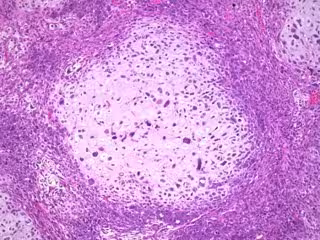

Archivo - Sufrir un cáncer de mama predispone a desarrollar un cáncer ginecológico, según un estudio - WEBPATHOLOGY. VISUAL SURVEY OF SURGICAL PATHOLOGY